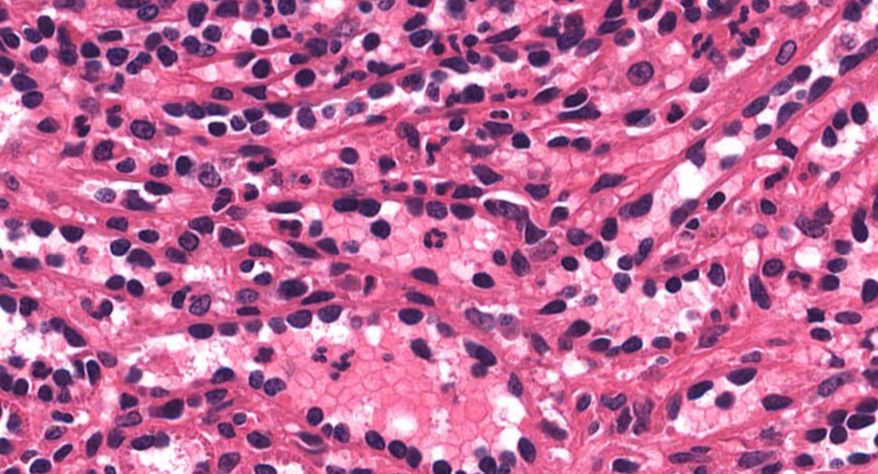

低倍镜:胸腺表面包有薄层结缔组织构成的被膜,结缔组织深入实质,将胸腺分成许多不完整的小叶。每个小叶分为周围的皮质和中央的髓质两部分。皮质中胸腺细胞排列密集,故染色深;髓质中胸腺细胞较少,胸腺上皮细胞多,故染色浅,其中可见染成红色的圆形小体-胸腺小体。高倍镜:胸腺小体大小不等,由几层至十几层扁平的胸腺上皮细胞呈同心圆状排列而成,其外周的细胞较幼稚,细胞核明显;小体中央部分的上皮细胞已退化,细胞核消失,胞质呈均质状,染成红色。